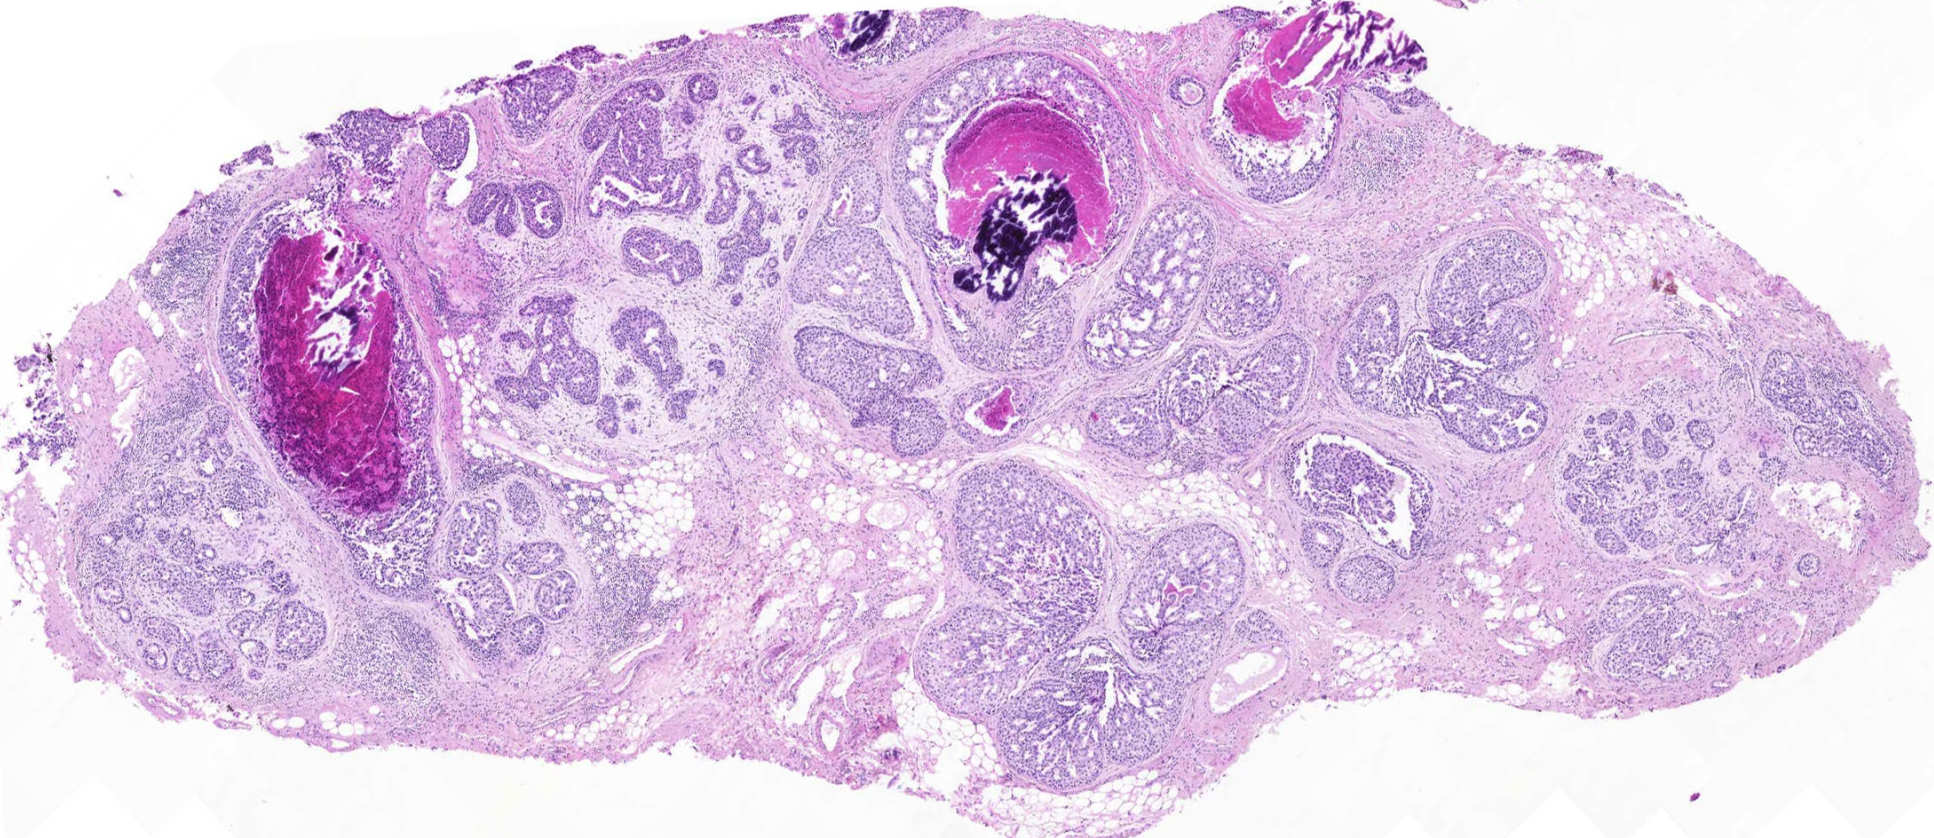

We are currently focused on two main areas of research: firstly, the analysis of DNA mutations in the normal and malignant breast and colon tissue; and secondly, the use of cancer-associated miRNA as potential biomarkers and therapeutic targets.

Breast and colon cancers are amongst the most commonly diagnosed neoplasms in the world. The basis of colitis-associated colon cancer and the effect of age of pregnancy on breast cancer occurrence are still not well-studied. Understanding these molecular mechanisms will enable better prevention strategies such as surveillance programs which could be implemented in clinical settings.

- Analysis of markers of proliferation and apoptosis in normal breast and breast cancer tissue from different time points in the reproductive age, recording age of pregnancy and of cancer onset

- Investigation of genetics and epigenetics changes of the normal and malignant breast and colon by detecting single nucleotide variants, insertions/deletions, copy number changes, and large structural variants